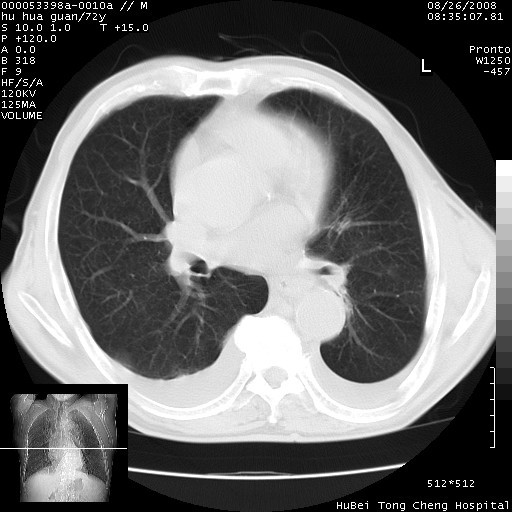

1、右上肺结节病变,肺泡癌不除外,请随诊;左下肺近后纵隔病变,考虑纵隔型肺癌侵犯大血管可能;

2、右下肺背段少许炎症,双侧胸腔积液,右下肺纤维索条。

可以明确的说。肯定不是主动脉夹层破裂出血!考虑为淋巴瘤或间叶组织来源的恶性肿瘤可能性大。右肺小结节建议薄层观察,如能发现恶性征象,那椎前改变就考虑为转移所致。至于双侧少量胸水乃静脉血回流受阻所致。

图像及窗宽窗位均不理想。周围性肺癌/胸腔积液/纵隔积液。

1、右肺周围性肺癌、胸腔积液(双)

降主动脉前移位,后纵隔占位

后纵隔占位,降主动脉前移位;双侧胸腔积液;应排外食管病变侵犯血管可能;